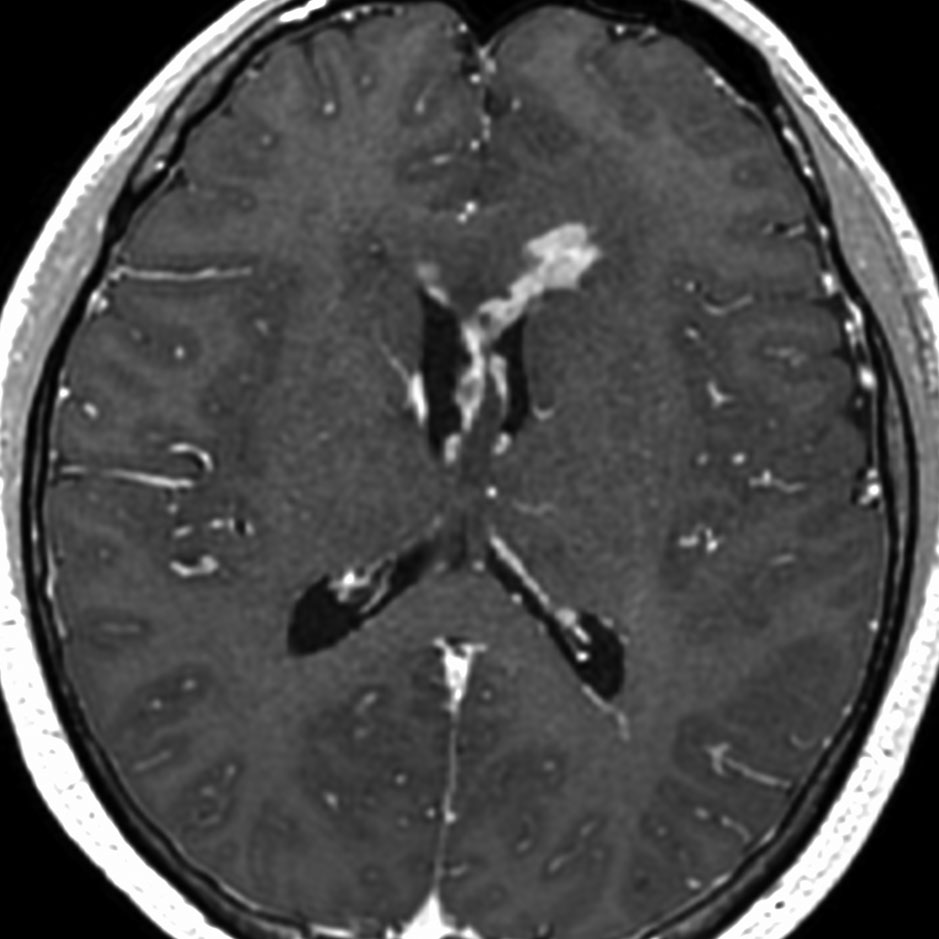

ガドリニウム増強では,前頭葉腫瘍というより,側脳室壁にベトベトくっついているような腫瘍です。germinoma特有のsubependymal infiltration像を示します。

生検後2ヶ月,セカンドオピニオンのために受診された時の画像です。腫瘍が縮小傾向にあります。入院中に行われた何度かのCT被曝の影響で,germinomaの退縮が生じたのだと判断しました。